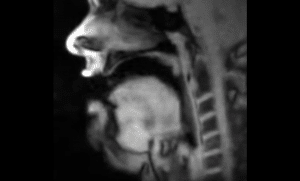

Nel video si vede la bocca di un uomo dall’interno mentre sta parlando.

Le immagini assai dettagliate sono state realizzate grazie alla ricerca sulla tomografia a risonanza magnetica (MRT).

Ecco il video che mostra l’interno della bocca di un uomo mentre parla e i movimenti della sua lingua: